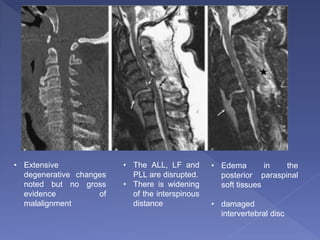

• Extensive

degenerative changes

noted but no gross

evidence of

malalignment

• The ALL, LF and

PLL are disrupted.

• There is widening

of the interspinous

distance

• Edema in the

posterior paraspinal

soft tissues

• damaged

intervertebral disc

Discontinuity of the ligamentum flavum and

edema in the posterior paraspinal

musculature